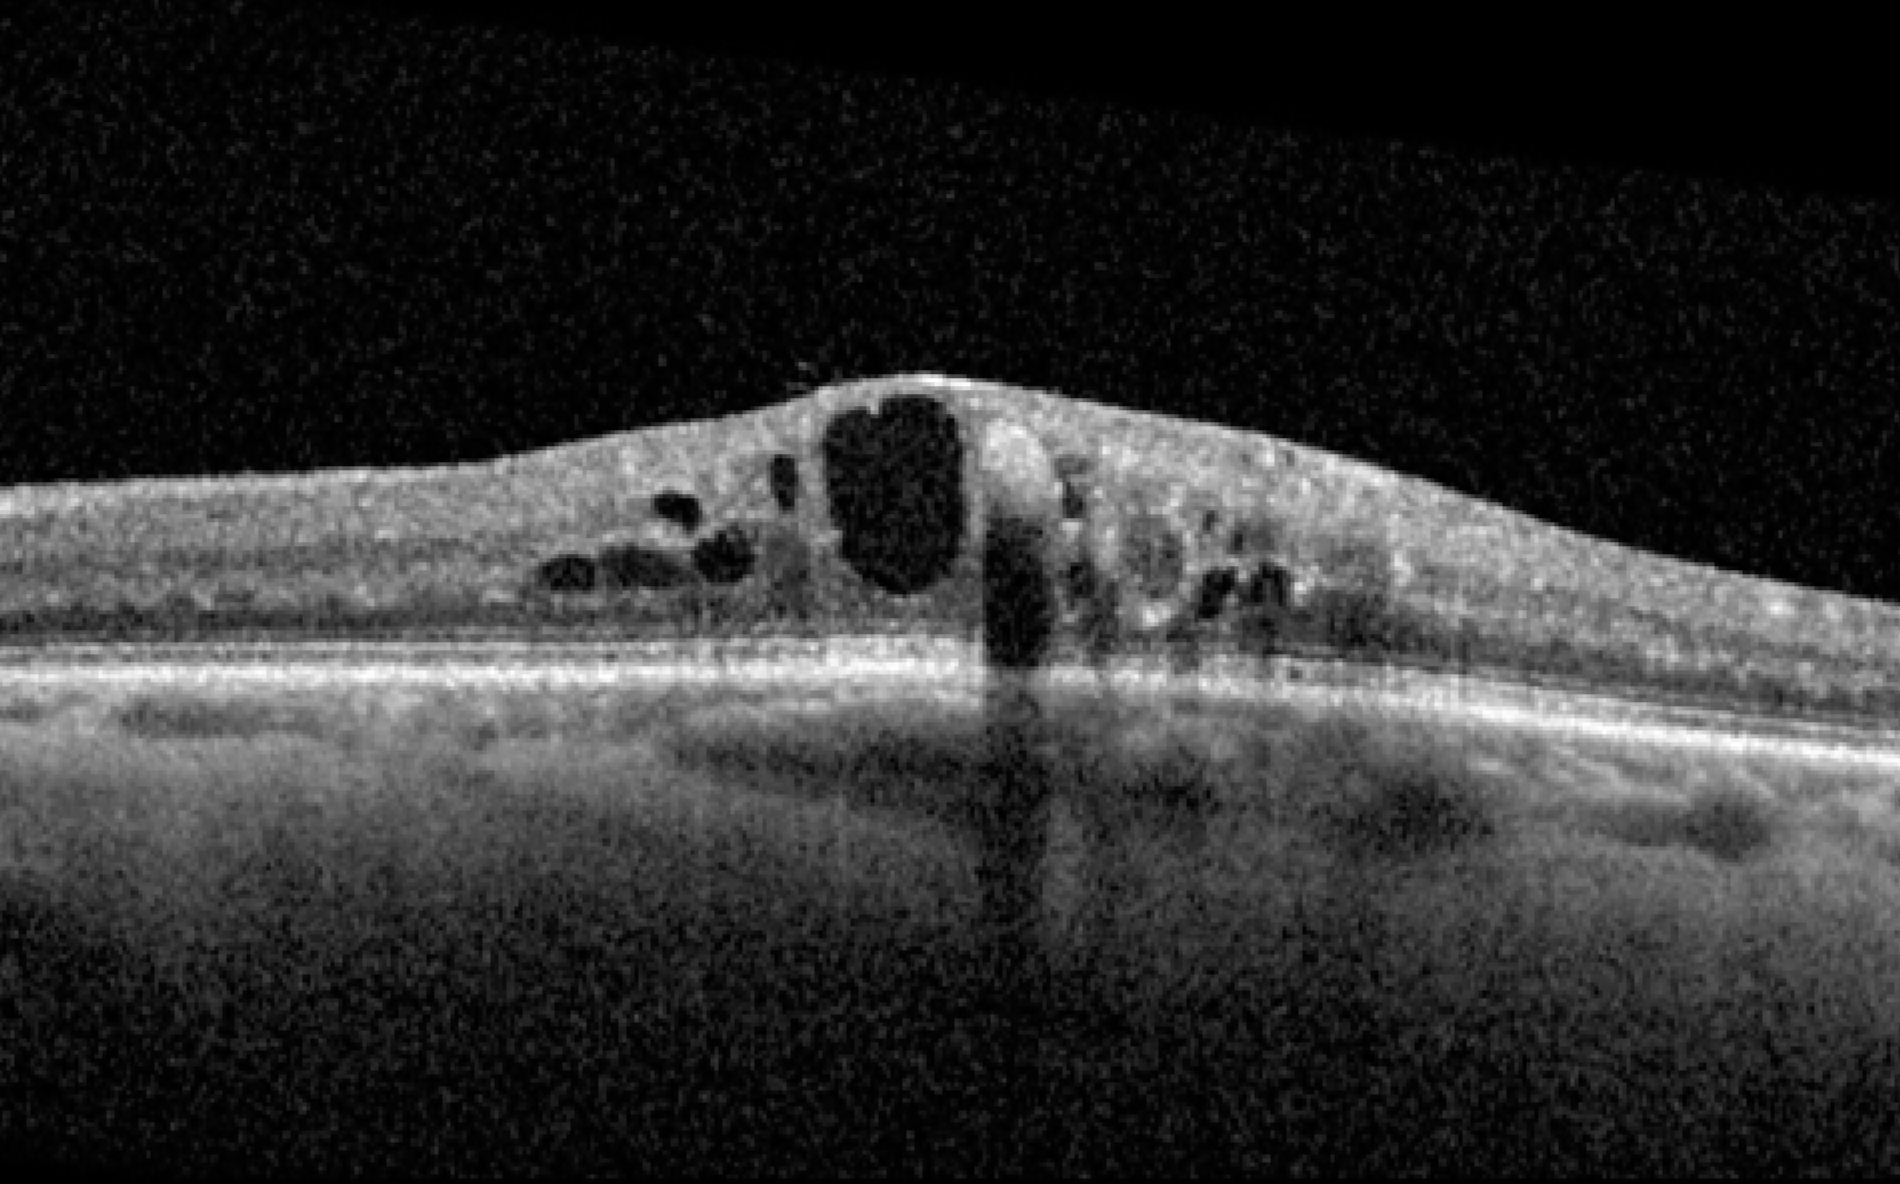

Macular Degeneration

Age-Related Macular Degeneration (AMD)

Intravitreal injection for Wet AMD and Advanced Geographic Atrophy.